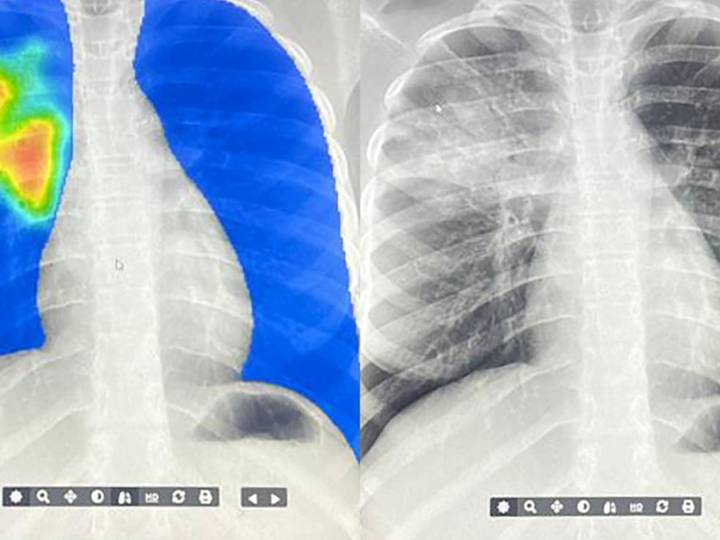

The difference? A mobile x-ray machine and an AI algorithm are detecting TB. (In case you're not familiar with AI terminology — this is basically a computer program trained on a whole lot of data.)